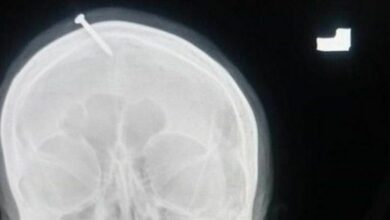

ตร. ปากีฯ ตามล่า หมอผีตอกตะปู ลงหัวหญิงตั้งท้อง

เจ้าหน้าที่ตำรวจในปากีสถานตามล่าตัวของ หมอผีตอกตะปู ลงหัวหญิงตั้งท้อง 3 เดือน โดยสัญญาว่าพิธีดังกล่าวจะช่วยให้เธอกำเนิดบุตรชาย เมื่อวันที่ 9 กุมภาพันธ์ สำนักข่าว BBC รายงานว่า เจ้าหน้าที่ตำรวจชาวปากีส